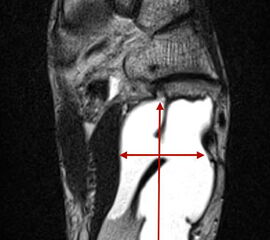

Die Magnetresonanztomographie erlaubt nicht nur die exakte Beurteilung der intramedul­lären und extraossären Tumorausdehnung einschließlich reaktiver Zone, sondern auch die genaue Lagebeziehung zu neurovaskulären Strukturen (Abb. 8) und eine Differenzierung zwischen vitalen versus nekrotischen Tumoranteilen. Dies ist insbesondere für eine mögliche Biopsie von entscheidender Bedeutung um repräsentatives Tumorgewebe für die histo­patho­logische Analyse gewinnen zu können. Die bei Verdacht auf einen Knochen- oder Weichteiltumor vom Radiologen durchzuführenden Standardprotokolle der MRT wurden im Jahr 2006 von der Arbeitsgemeinschaft Muskuloskelettale Diagnostik der Deutschen Röntgengesellschaft veröffentlicht (Tab.2) und gewähren bei entsprechender Umsetzung eine qualitativ hochwertige Untersuchung (DRG, 2006).

MR-tomographische Darstellung eines unspezifischen weichteiligen Raumforderug im Bereich des dorso-lateralen Rückfußes. Die offene Probebiopsie ergab schließlich die Diagnose eines hochmalignen Synovialsarkoms.

Abbildung 34